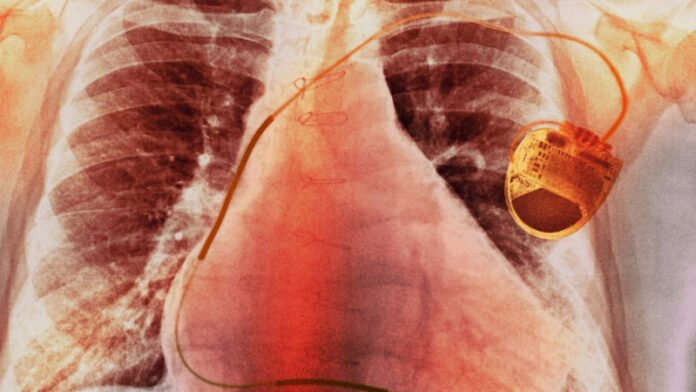

Egy kínai kutatócsoport áttörést ért el a szívritmus-szabályozás területén: olyan önellátó pacemakert fejlesztettek ki, amely a szív saját mozgásából termel elektromos energiát – írja a PCW. A Nature Biomedical Engineering magazinban bemutatott tanulmány szerint a hagyományos pacemakerek egyik legnagyobb problémáját oldja meg az eszköz, hiszen a jelenleg használt készülékek akkumulátorai nagyjából tíz évig biztosítanak energiát, ami ezen idő leteltével egy újabb, kockázatos és költséges műtétet tesz szükségessé.

A kapszula méretű, vezeték nélküli pacemaker biokompatibilis anyagokból készült, és minimálisan invazív eljárással, a combvénán keresztül ültethető be. Teljesítménye átlagosan 120 mikrowatt, ami bőven meghaladja a stabil működéshez szükséges 10 mikrowattot. Egy egy hónapos állatkísérlet során egy súlyos szívritmuszavarral küzdő sertésben a készülék kizárólag a szív saját energiáját felhasználva tartotta fenn a normál ritmust.